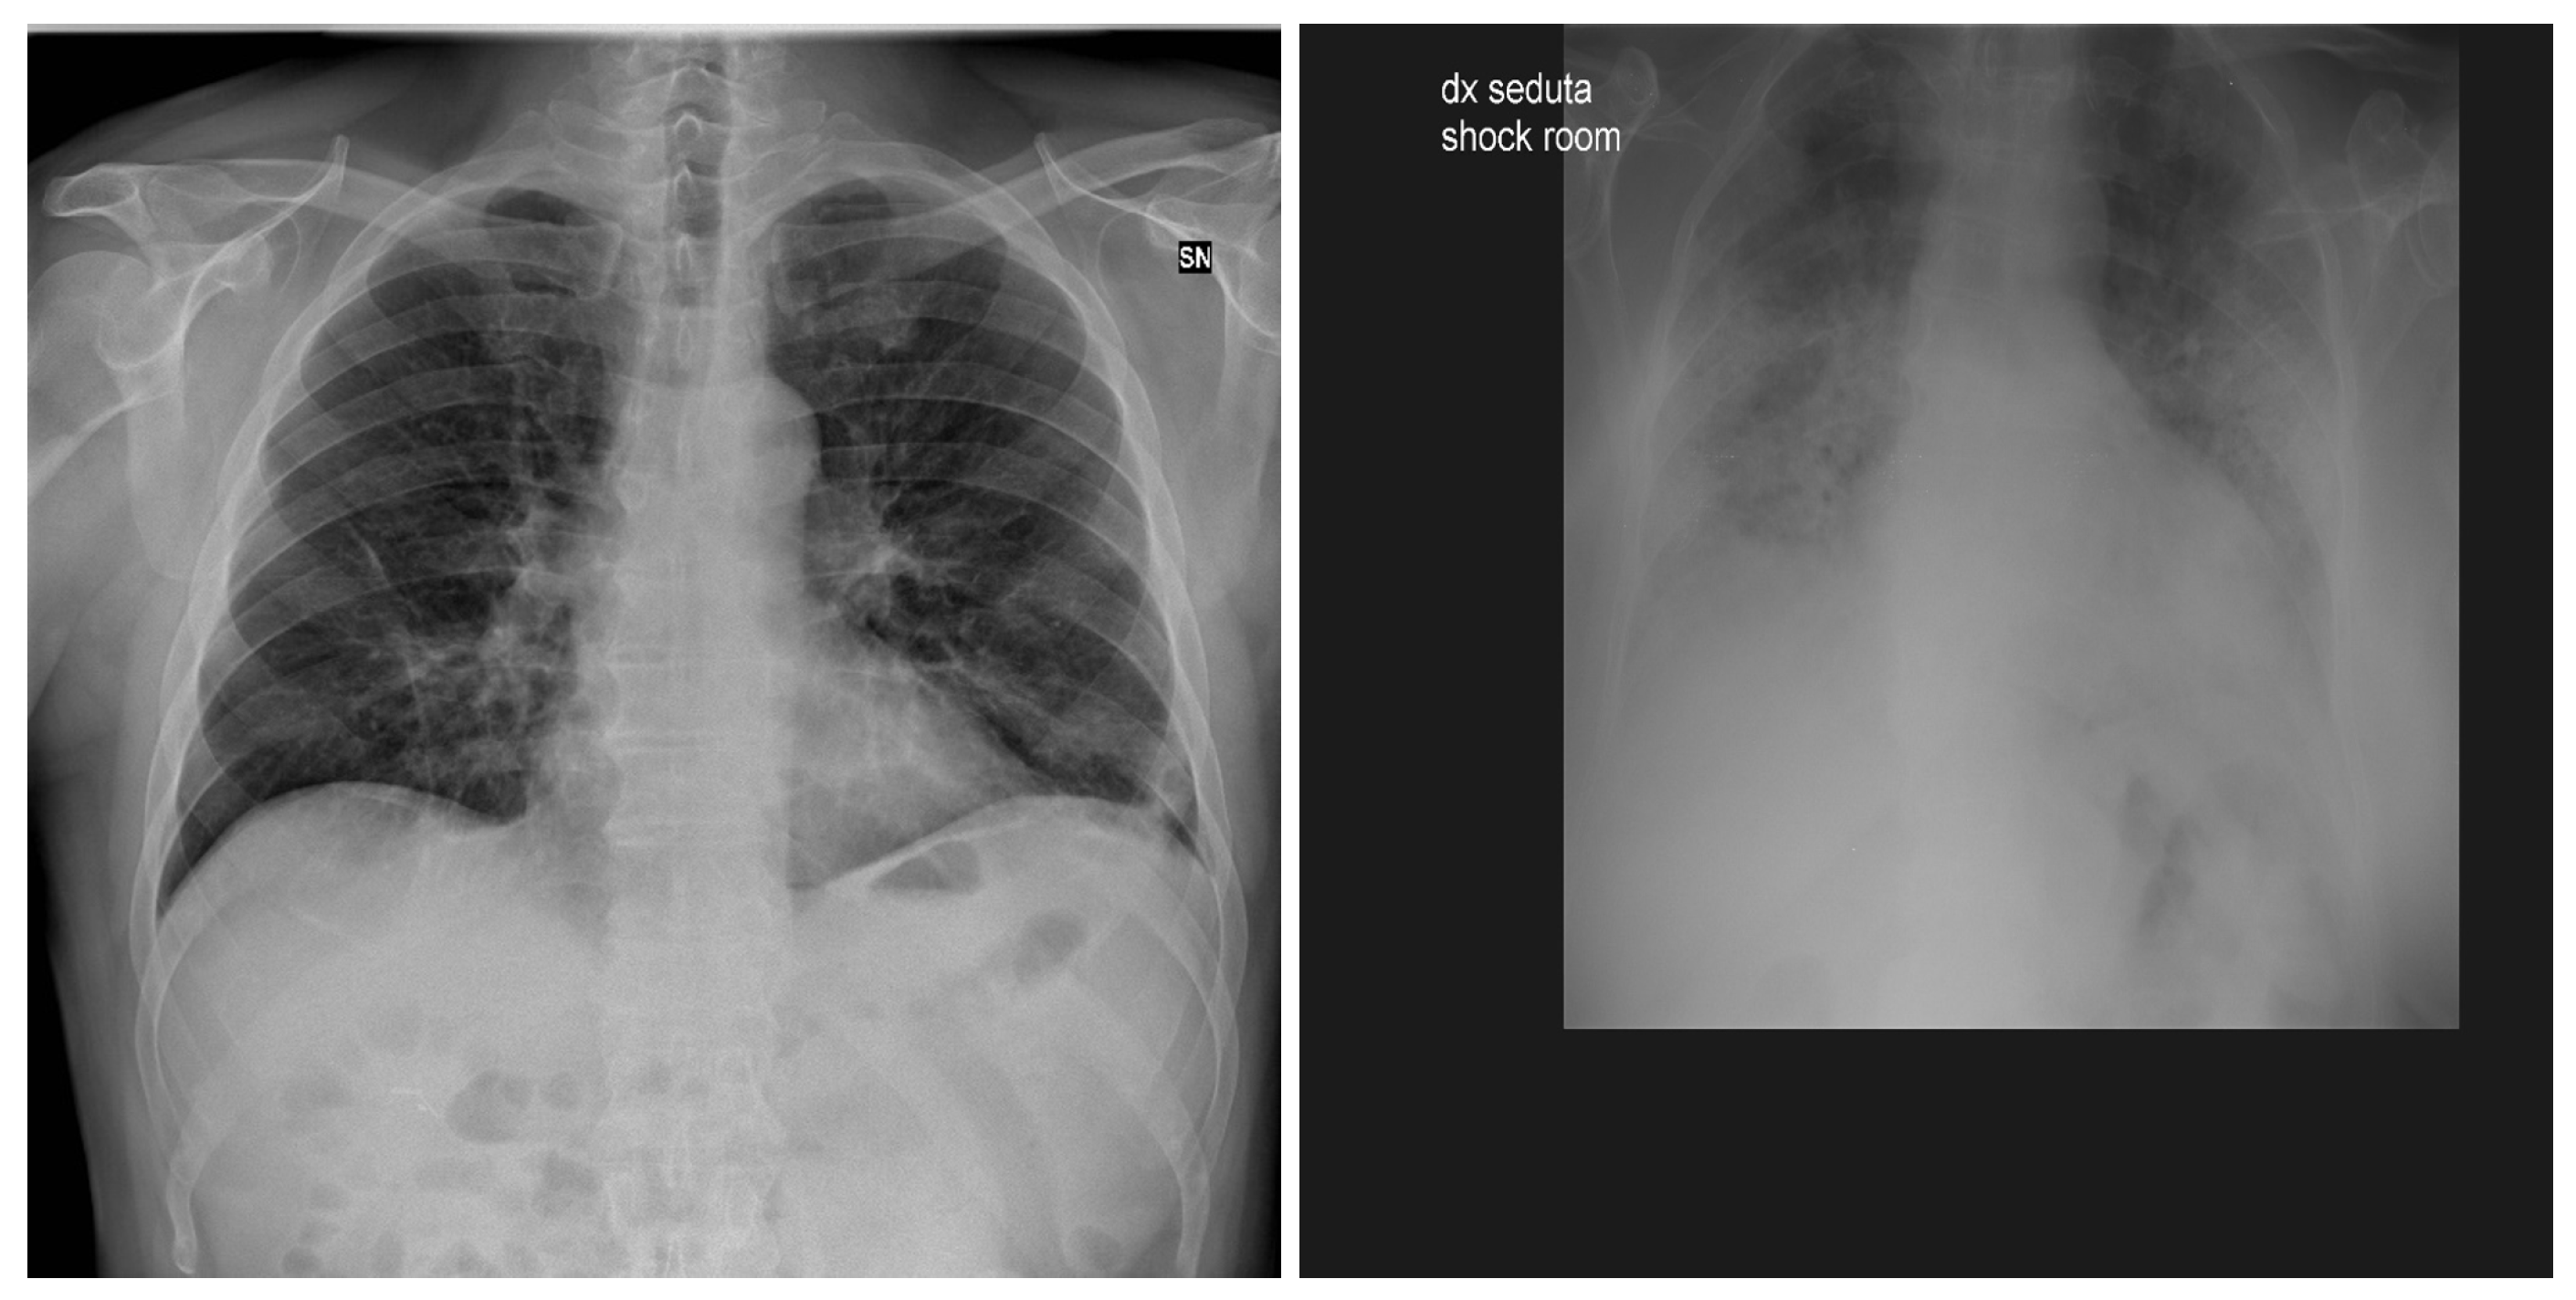

3.3. BIMCV COVID19+

5. Individual Tests